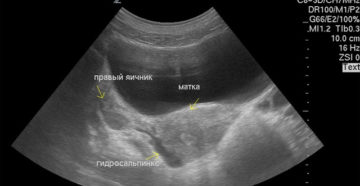

Беременность при гидросальпинксе: можно или нет Можно ли забеременеть при Гидросальпинксе? Подобный вопрос беспокоит абсолютно…